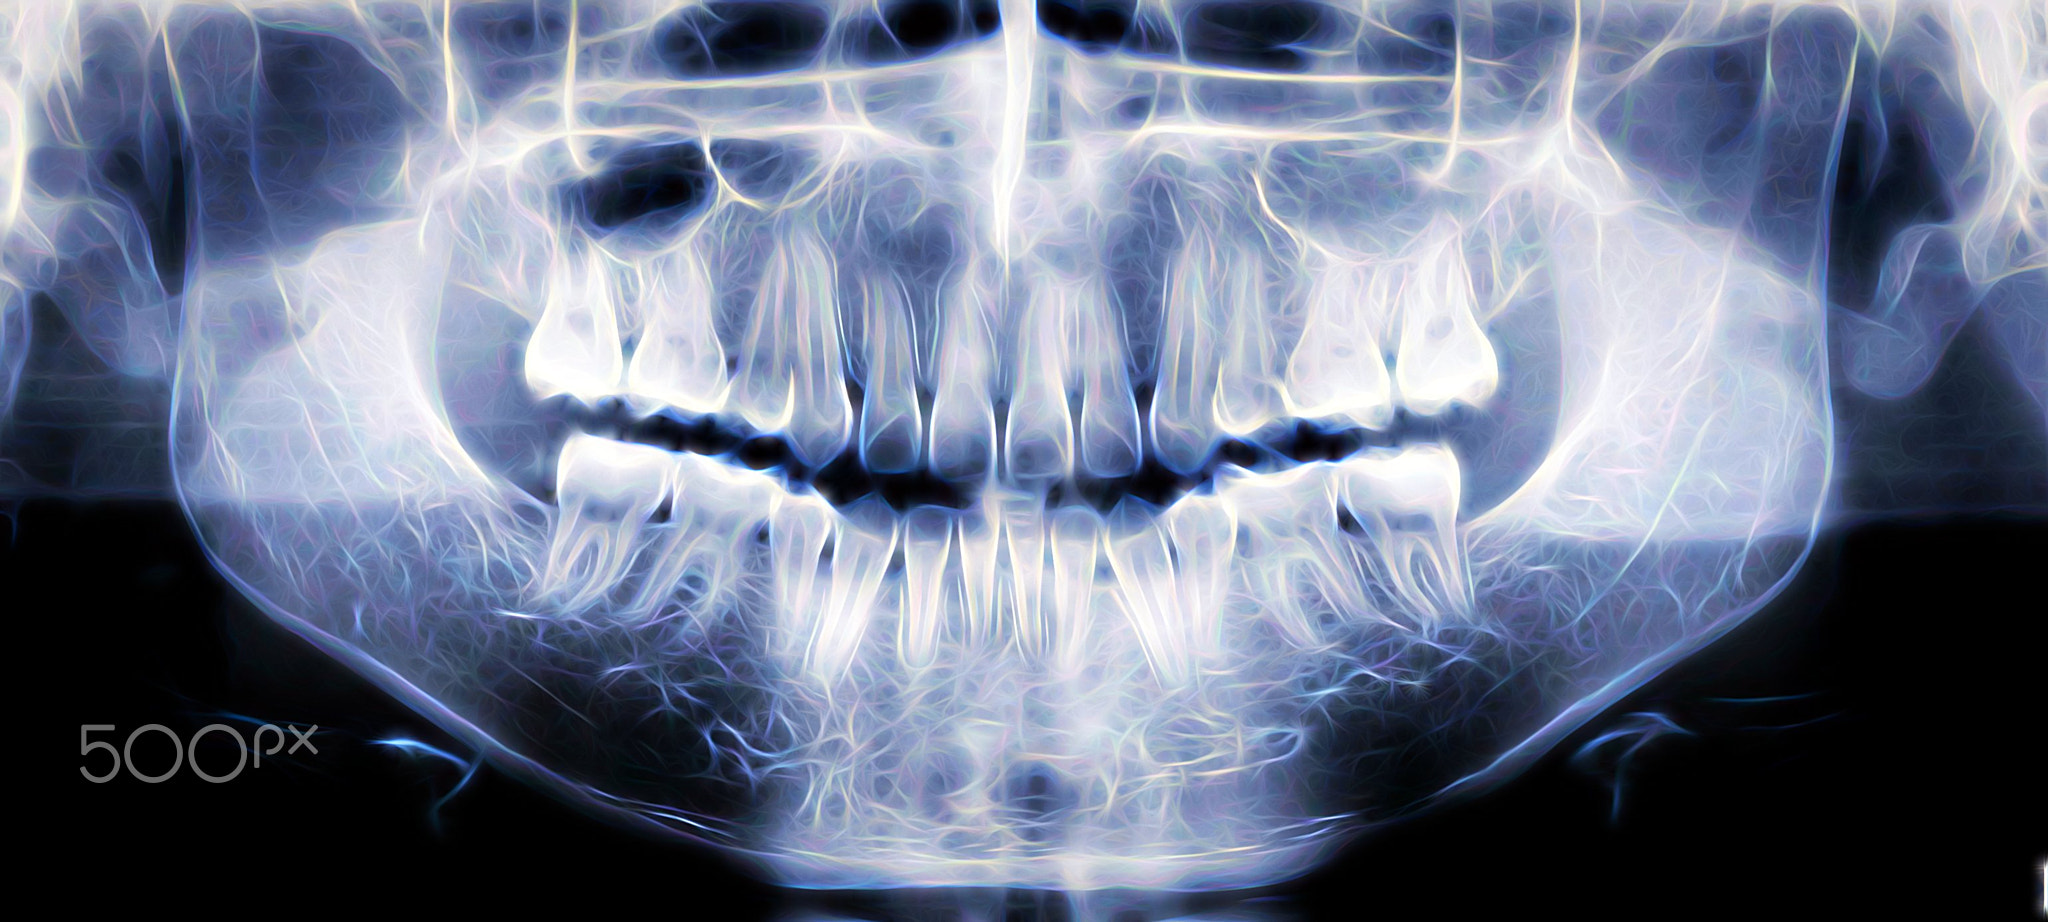

Los rayos X son una forma de radiación electromagnética que puede pasar a través del cuerpo y producir imágenes detalladas de los huesos y otras estructuras internas.

En la atención ortopédica, los rayos X se han convertido en una herramienta indispensable para el diagnóstico de diversas afecciones musculoesqueléticas, la evaluación de las fracturas óseas y el seguimiento del proceso de curación después de las intervenciones quirúrgicas.

En ortopedia, una cicatrización adecuada es vital para recuperar la movilidad y la funcionalidad. Las radiografías desempeñan un papel fundamental en el seguimiento del proceso de curación de fracturas, incisiones quirúrgicas y prótesis articulares. Al tomar radiografías en las distintas fases del proceso de curación, los profesionales médicos pueden observar la formación del callo óseo y la regeneración de los tejidos.